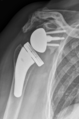

- Différentes lésion labrales post.jpg Alexandre.laedermann

19:53, 26 January 2020

1,918 × 454; 739 KB